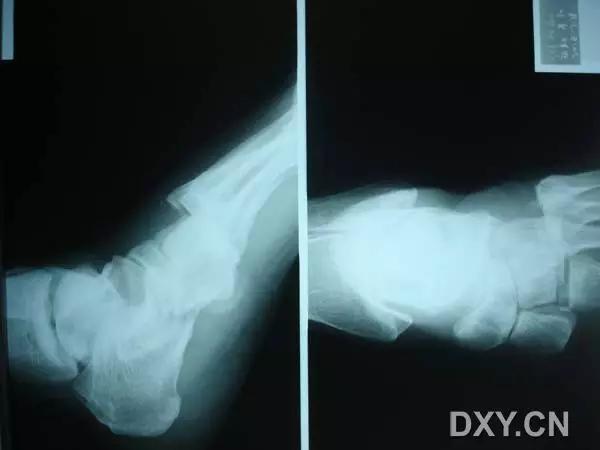

6. Pilon 骨折

涉及负重关节面(胫距关节面)与胫骨远侧干骺端的骨折。其典型特征是干骺端存在不同程度的压缩、干骺端的压缩粉碎性骨折不稳定、原发性关节软骨损伤以及永久性关节面不平整导致预后不良。

pilon 骨折正位片

pilon 骨折侧位片

pilon 骨折三维 CT 表现